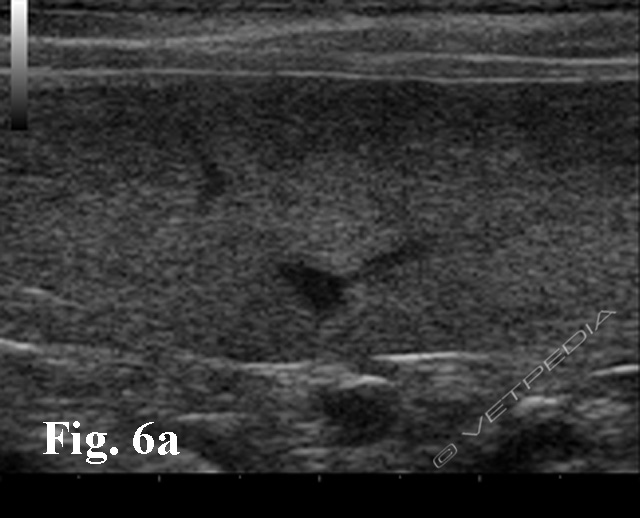

La durata del periodo di incubazione è altamente variabile in base al ceppo e alla specie interessata (generalmente da una a tre settimane). Occasionalmente possono verificarsi forme iperacute caratterizzate da tempi d’incubazione più brevi. I sintomi precoci della malattia sono febbre e disoressia cui seguono perdita di peso, anemia, trombocitopenia, splenomegalia, ittero, e soprattutto emoglobinuria, seguite da mialgie e talvolta dolore alla palpazione della loggia renale (segno del Giordano positivo) per l’effetto nefrotossico dell’emoglobina sui tubuli renali (Figg. 5, 6a e 6b; Video).